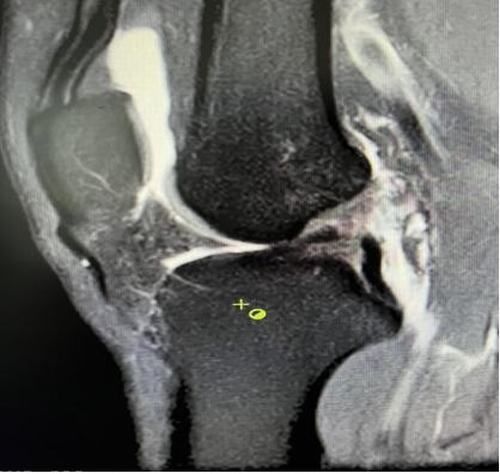

膝关节韧带损伤磁共振

我院骨科三病区近期收治了4名膝关节交叉韧带损伤患者。25岁的齐先生,因打篮球时不慎扭伤左膝,致右膝肿痛,遂来我院治疗;30岁赵先生酷爱足球,扭伤右膝关节来我院就诊;50岁的张先生、42岁刘先生因骑车滑倒摔伤、膝关节肿痛不适、活动受限,收治入院。骨科三病区李鹏主任团队详细查体以及完善影像学检查后进行诊断:几位患者共同诊断均有“前交叉韧带损伤”,不同程度合并有“半月板损伤”、“股骨软骨损伤”、“内侧副韧带断裂”。